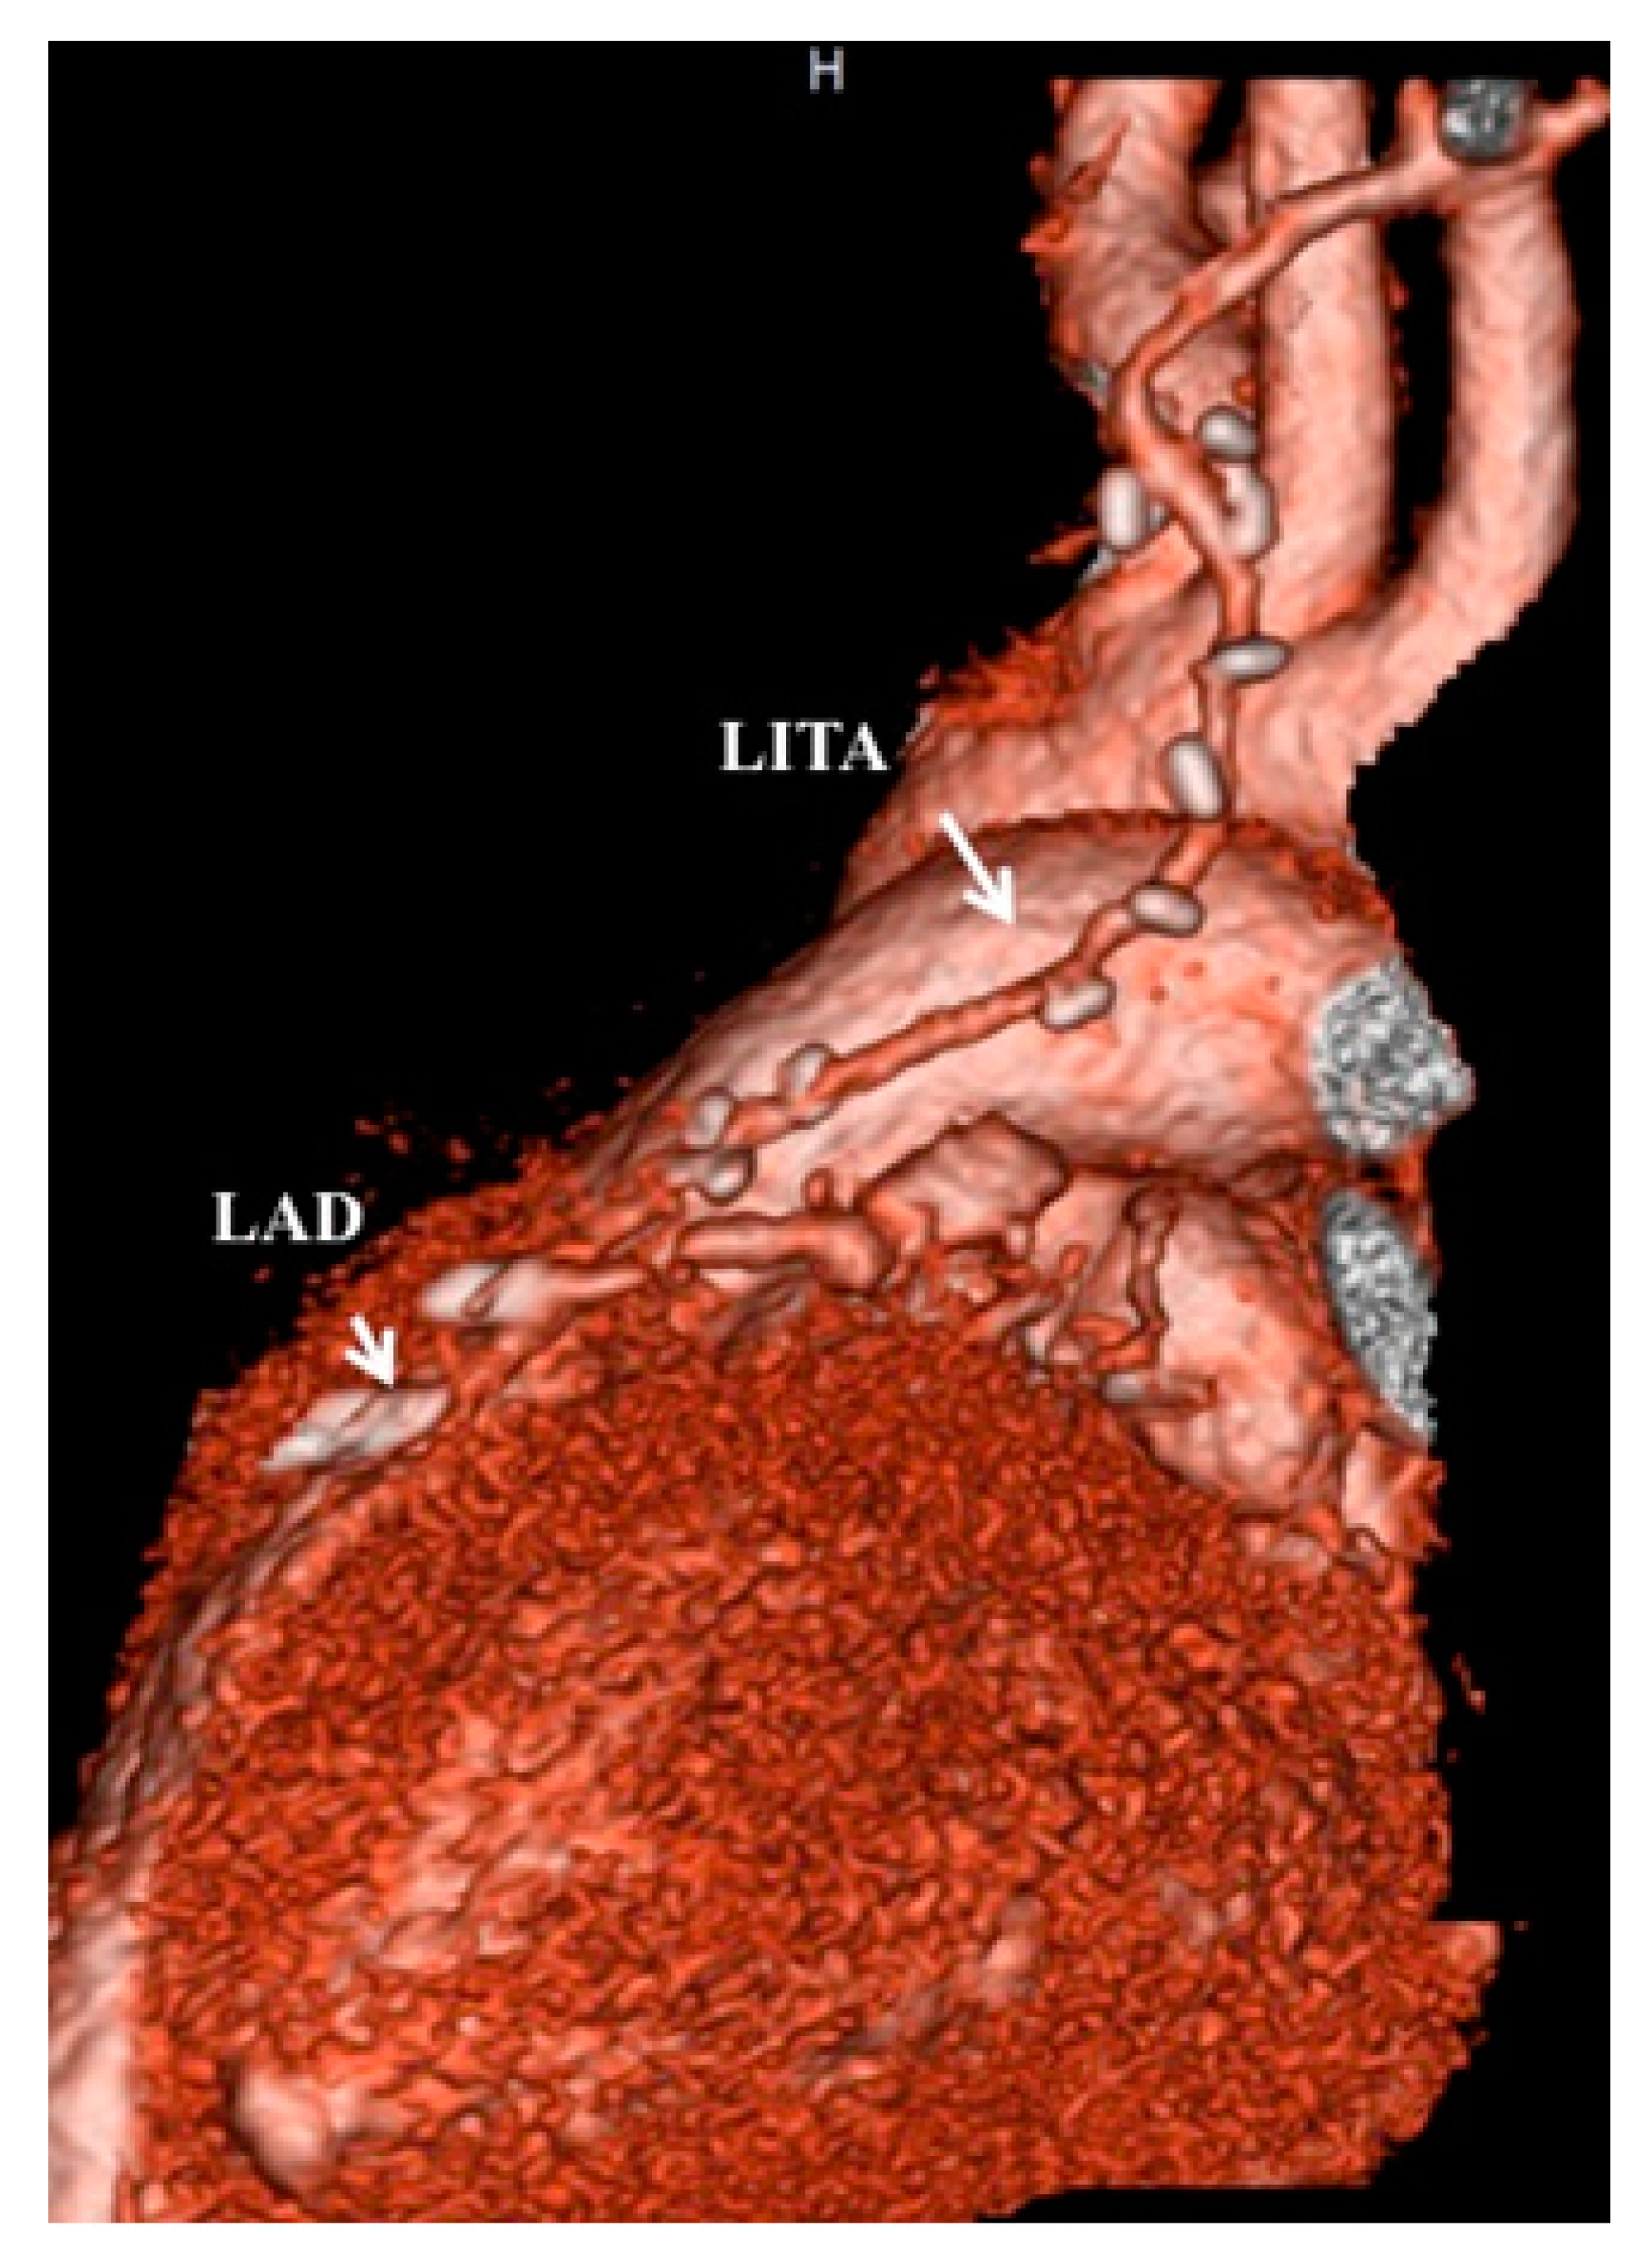

- Tsuda, E.; Kitamura, S.; Kimura, K.; Kobayashi, J.; Miyazaki, S.; Echigo, S.; Yagihara, T. Long-term patency of internal thoracic artery grafts for coronary artery stenosis due to Kawasaki disease: Comparison of early with recent results in small children. Am. Heart J. 2007, 153, 995–1000. [Google Scholar] [CrossRef] [PubMed]

- Kitamura, S.; Tsuda, E.; Kobayashi, J.; Nakajima, H.; Yoshikawa, Y.; Yagihara, T.; Kada, A. Twenty-five-year outcome of pediatric coronary artery bypasss surgery for Kawasaki disease. Circulation 2009, 120, 60–68. [Google Scholar] [CrossRef] [PubMed]

- Kitamura, S.; Seki, T.; Kawachi, K.; Morita, R.; Kawata, T.; Mizuguchi, K.; Kobayashi, S.; Fukutomi, M.; Nishii, T.; Kobayashi, H.; et al. Excellent patency and growth potential of internal mammary artery grafts in pediatric coronary bypass surgery: New evidence for a “live” conduit. Circulation 1989, 78, I129–I139. [Google Scholar]